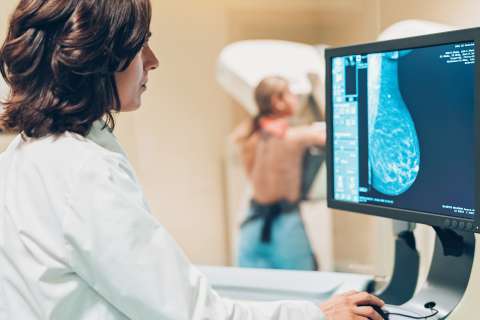

3D mammograms (breast tomosynthesis): Mammograms are low-dose breast X-rays. A technician takes X-rays from several views and a computer compiles those images into a 3D picture that allows us to see breast tissue clearly.

Screening mammogram: We perform screening mammograms for patients who have no signs of breast cancer. These tests involve two views of the breast. Screening mammograms are one of the best tools we have for finding cancer in early stages.

Diagnostic mammogram: If a patient has symptoms that could point to breast cancer, we do a diagnostic mammogram. It involves several views of the breast and focuses on particular areas of concern. We can use these tests to diagnose the cause of breast changes, such as an unusual lump, pain or nipple discharge.